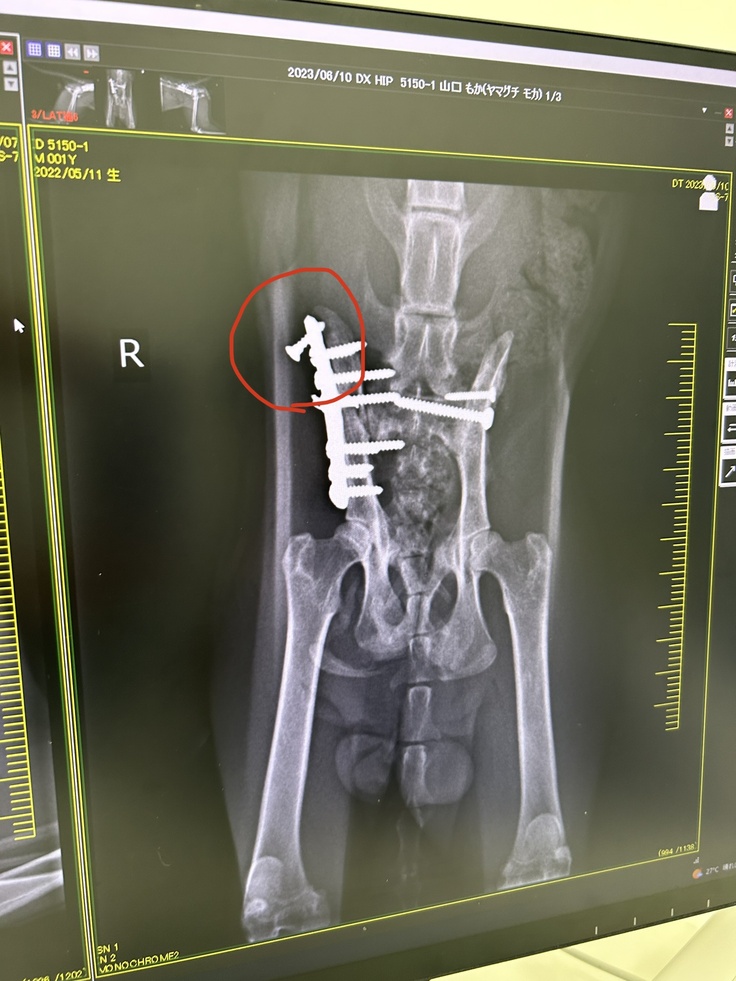

レントゲンを撮ると、前回取れかかっていた

ボルトは完全に取れていました。

↓前回のレントゲン写真